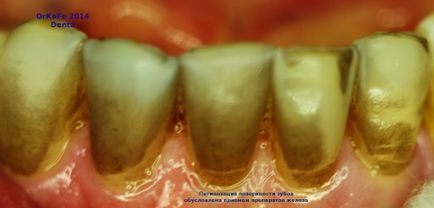

Un exemplu proaspăt de colorare externă a dinților de către compușii de fier (colorarea alimentară cu medicamente pentru anemia de deficit de fier).

Pacientul nu cunoștea adevăratul motiv al efectului compușilor de fier asupra dinților și a fost impresionat de rezultatul plăcut surprins după curățarea dinților cu o pastă abrazivă profesională pe bază de silicat de zirconiu.